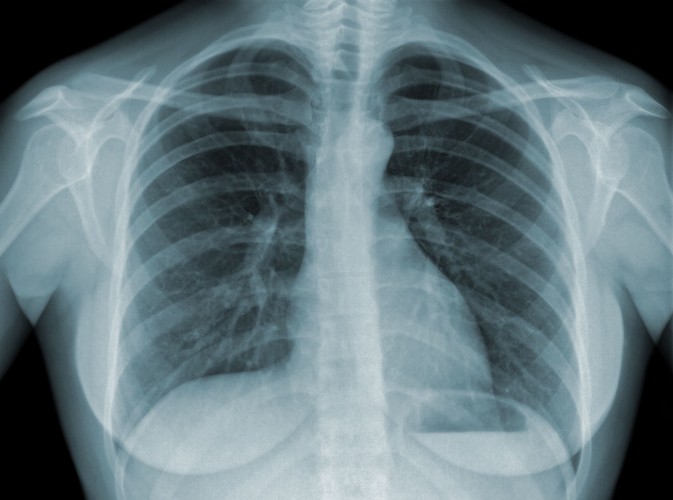

5 Gruźlica powstaje w wyniku zakażenia prątkami tej choroby. Najbardziej charakterystyczną dla gruźlicy histologiczną zmianą jest guzek, czyli gruzełek gruźliczy. W jego obrębie dochodzi do martwicy i wytworzenia mas serowatych, składających się ze zniszczonych tkanek i prątków. Poszczególne gruzełki mogą się ze sobą zlewać. W wyniku rozpływania się martwiczych mas i ich wypadania często powstają jamy, najczęściej w płucach